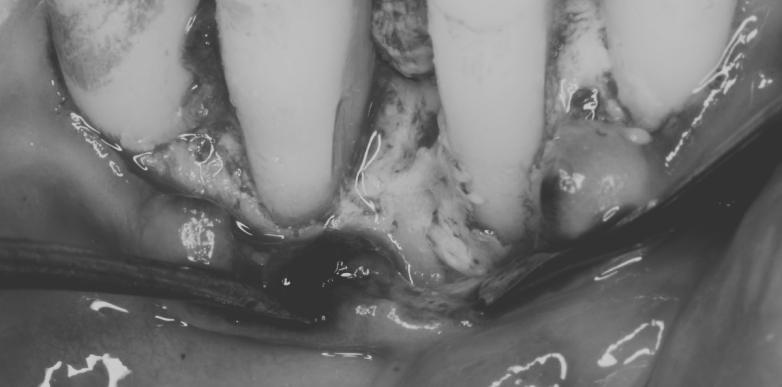

治療名 【歯周・歯内複合病変】組織再生療法+精密根管治療 治療期間 約1年 執刀医 Dr. 大杉 治療費 420,000円(税込)

■内訳:

再生療法 250,000円

根管治療 130,000円

支台築造 40,000円治療解説 歯の内部と歯周組織の両方に感染が及んでおり、抜歯判断になりやすいケースに対して保存を前提に治療を行いました。

まず精密根管治療で感染源を除去・封鎖し、その後に歯周組織再生療法を実施。

内外の感染を段階的にコントロールすることで、抜歯回避と安定化を目指しました。リスク・副作用 神経(歯髄)を除去するため、歯への栄養供給が断たれ、健全歯に比べて強度が低下します。

硬いものを噛んだ際などに歯根破折のリスクが伴う。 -